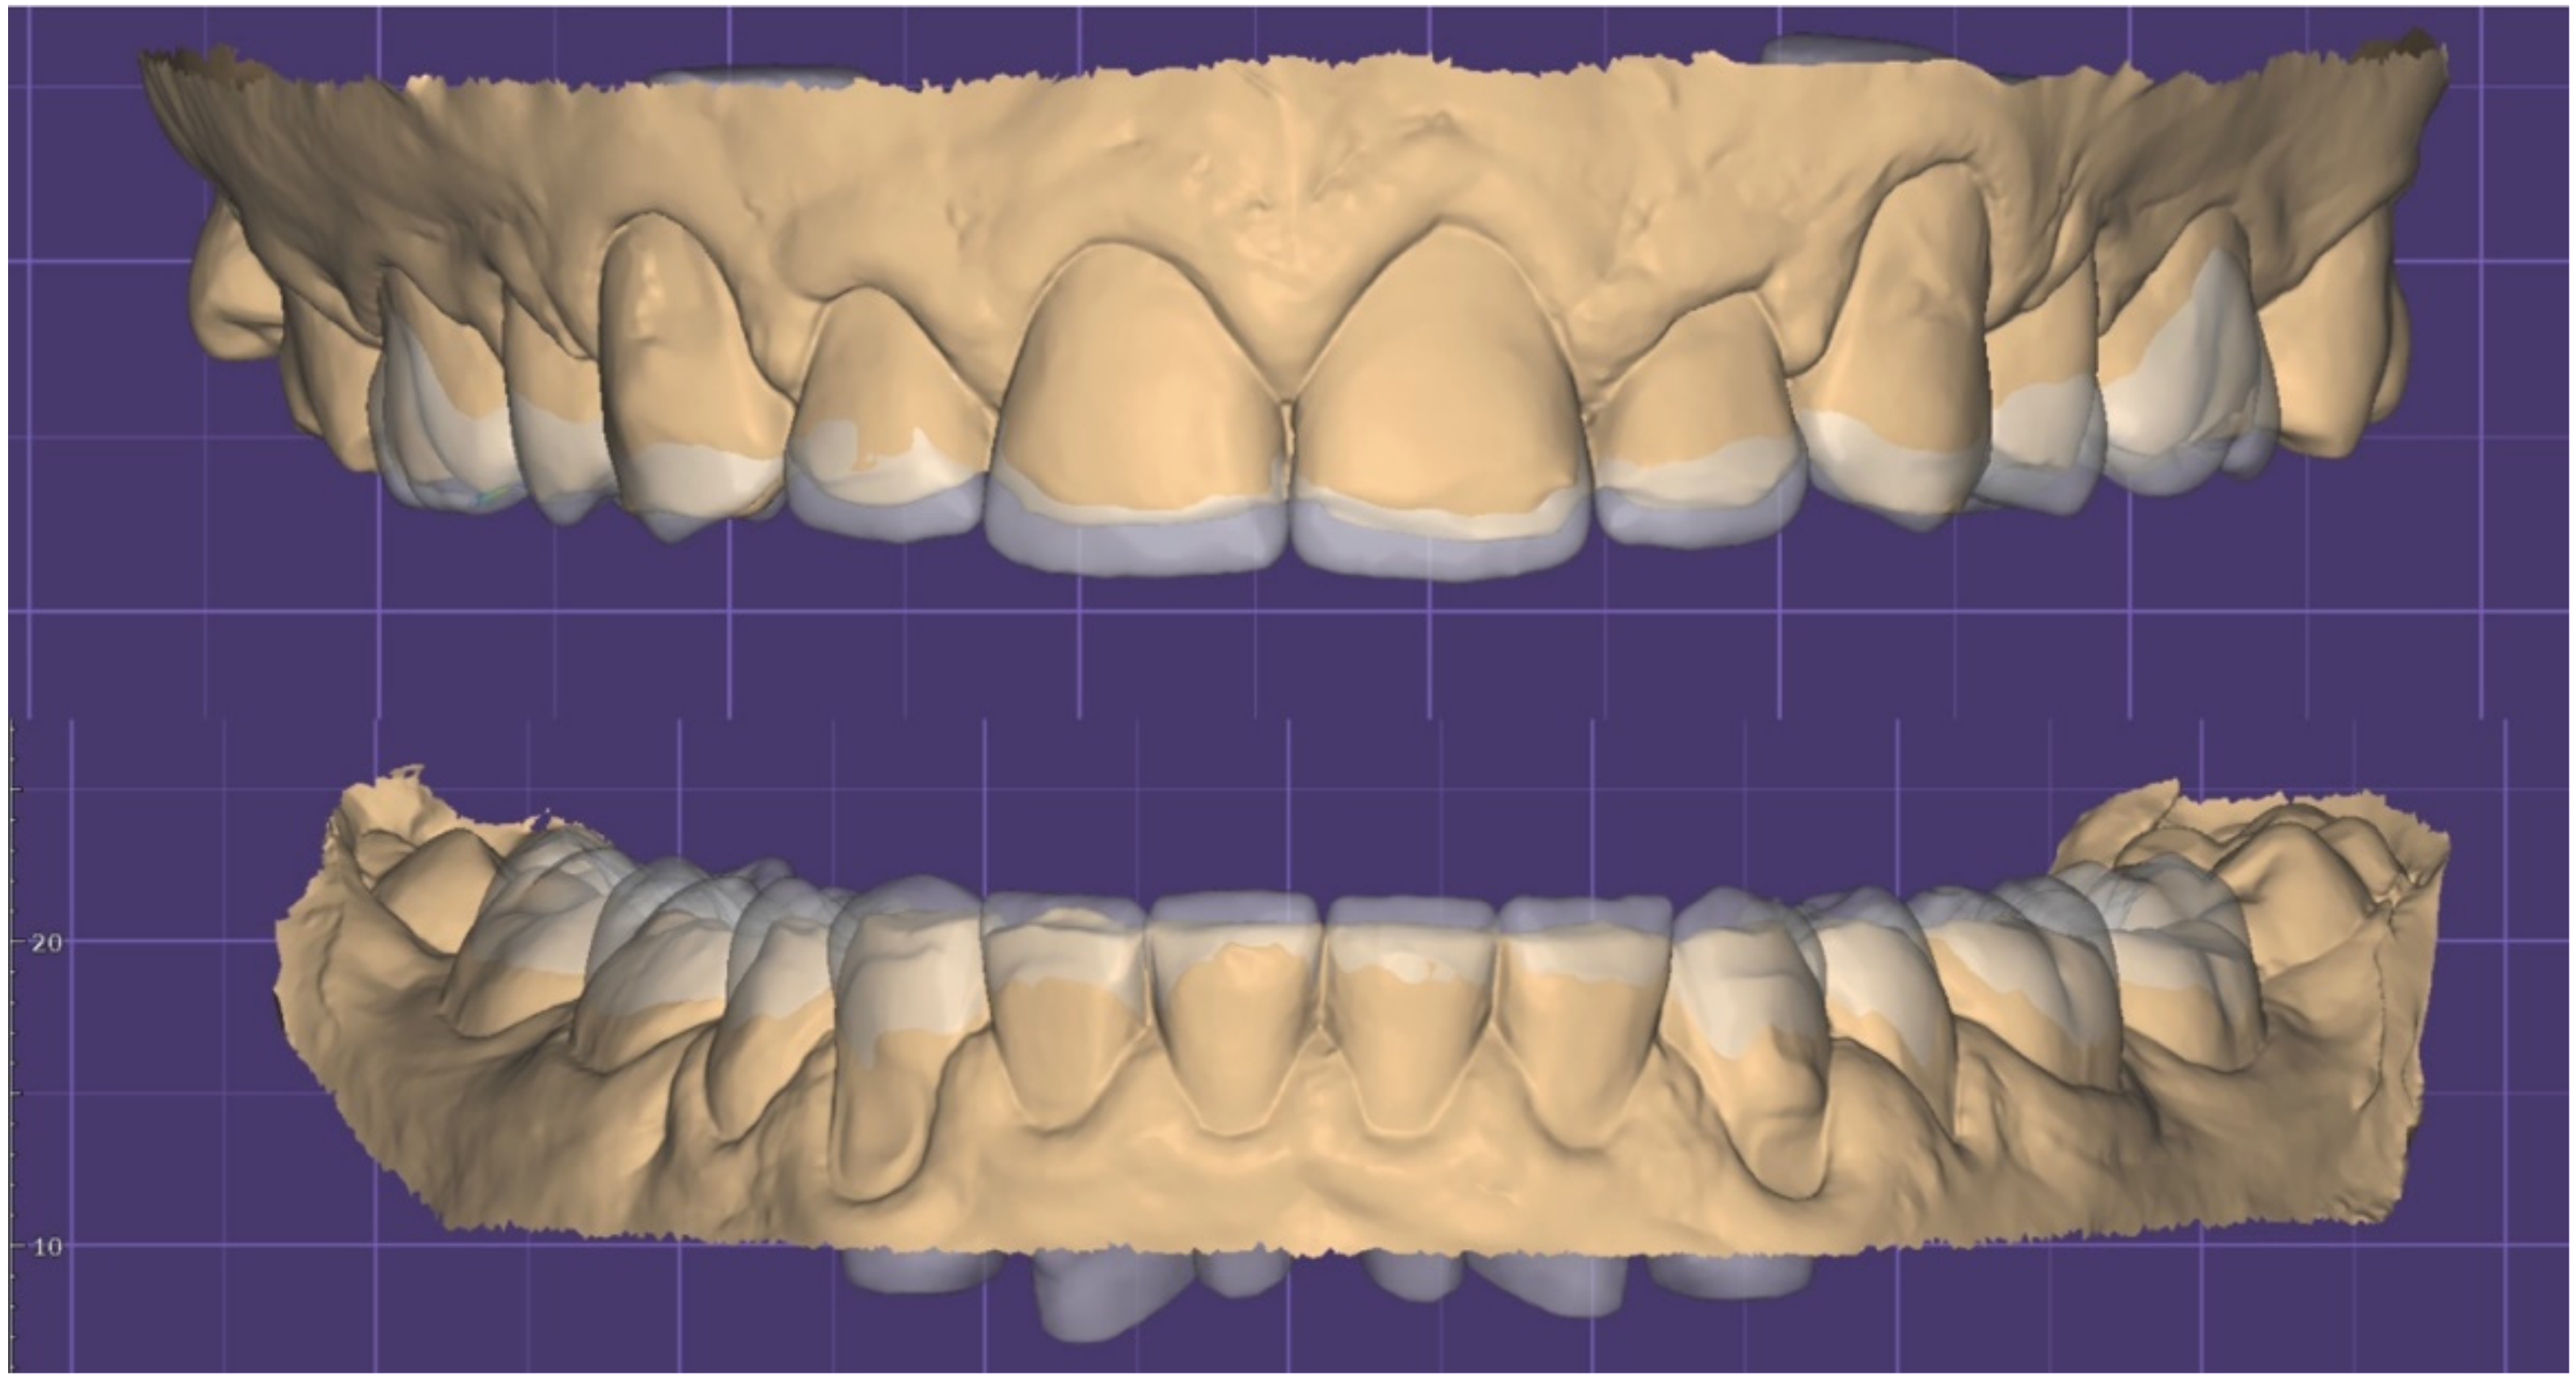

2.1. Planning Phase